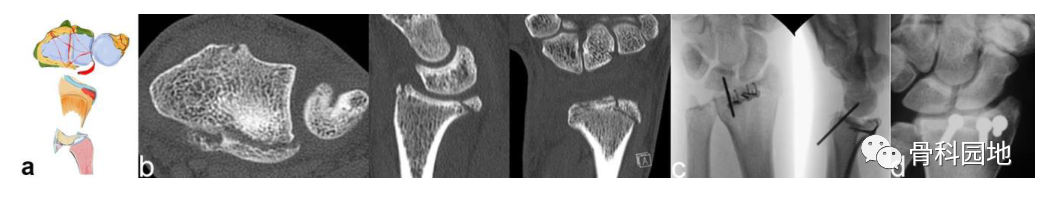

4、中央关键骨块

注:轴向作用力可导致关节面的中央塌陷或背侧和掌侧骨折块的爆裂性骨折(见图b)。这个中央关键骨块与轴或腕骨没有韧带连接。有时,它仅在关节面下略微凹陷,容易被忽视。如果这个中央骨块被更深地撞击到桡骨干中,则附着有稳定韧带的背侧和掌侧皮质骨都会像郁金香一样张开(见图 a)